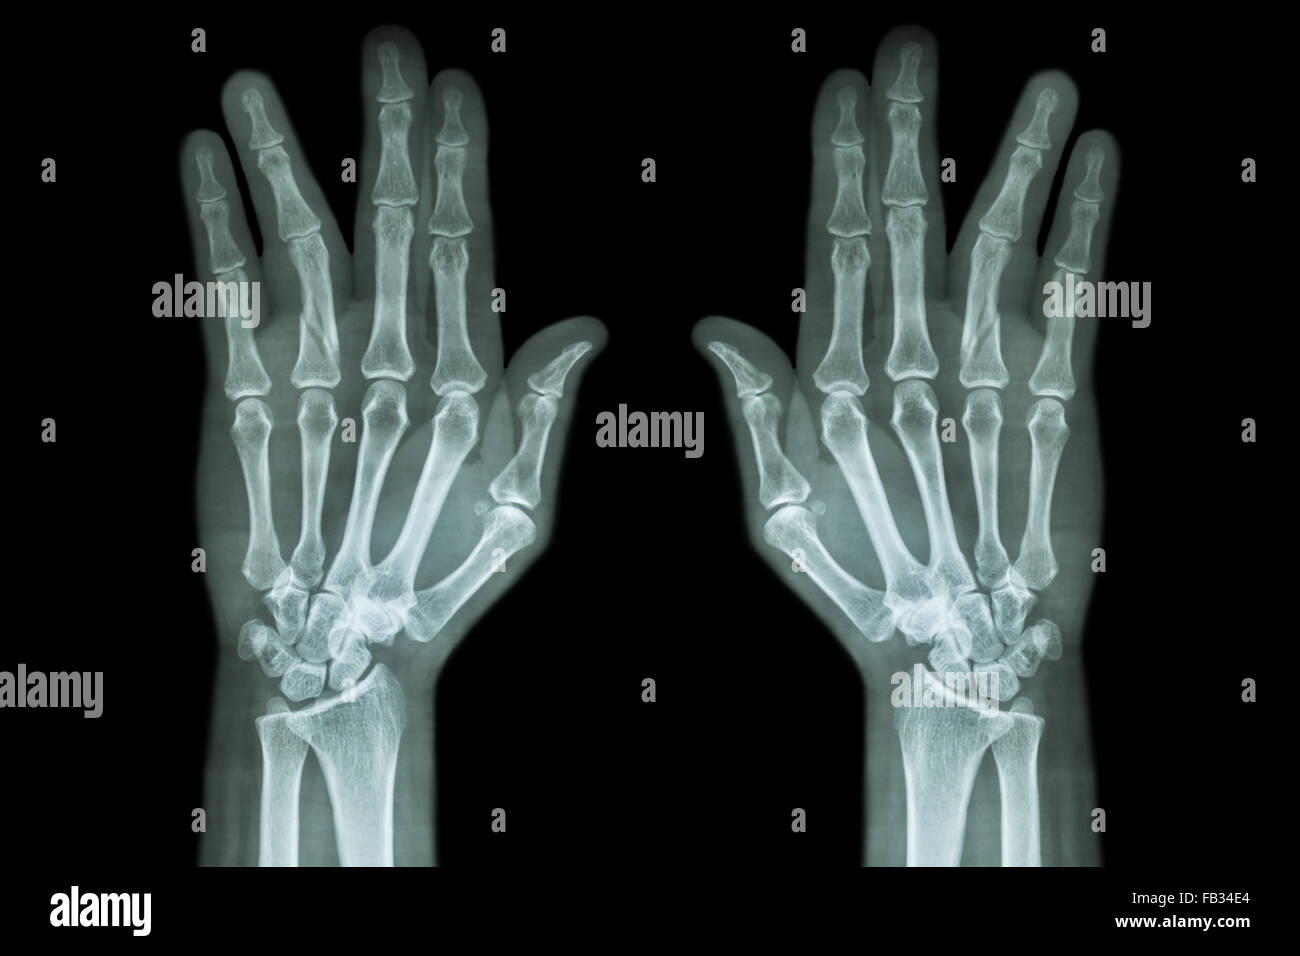

Finger Fracture X Ray . Tuft fracture (crush injury) soft tissue injury is often more obvious; Xray required to detect underlying fracture. Diagnosis can be confirmed with orthogonal radiographs of the involve. Phalanx fractures are common hand injuries that involve the proximal, middle or distal phalanx. The hand comprises the metacarpal and phalangeal bones. Fractures and dislocations are usually straightforward to identify, so long as the potentially injured bone is fully visible in 2 planes. Your doctor will also look for injuries to other nearby structures.